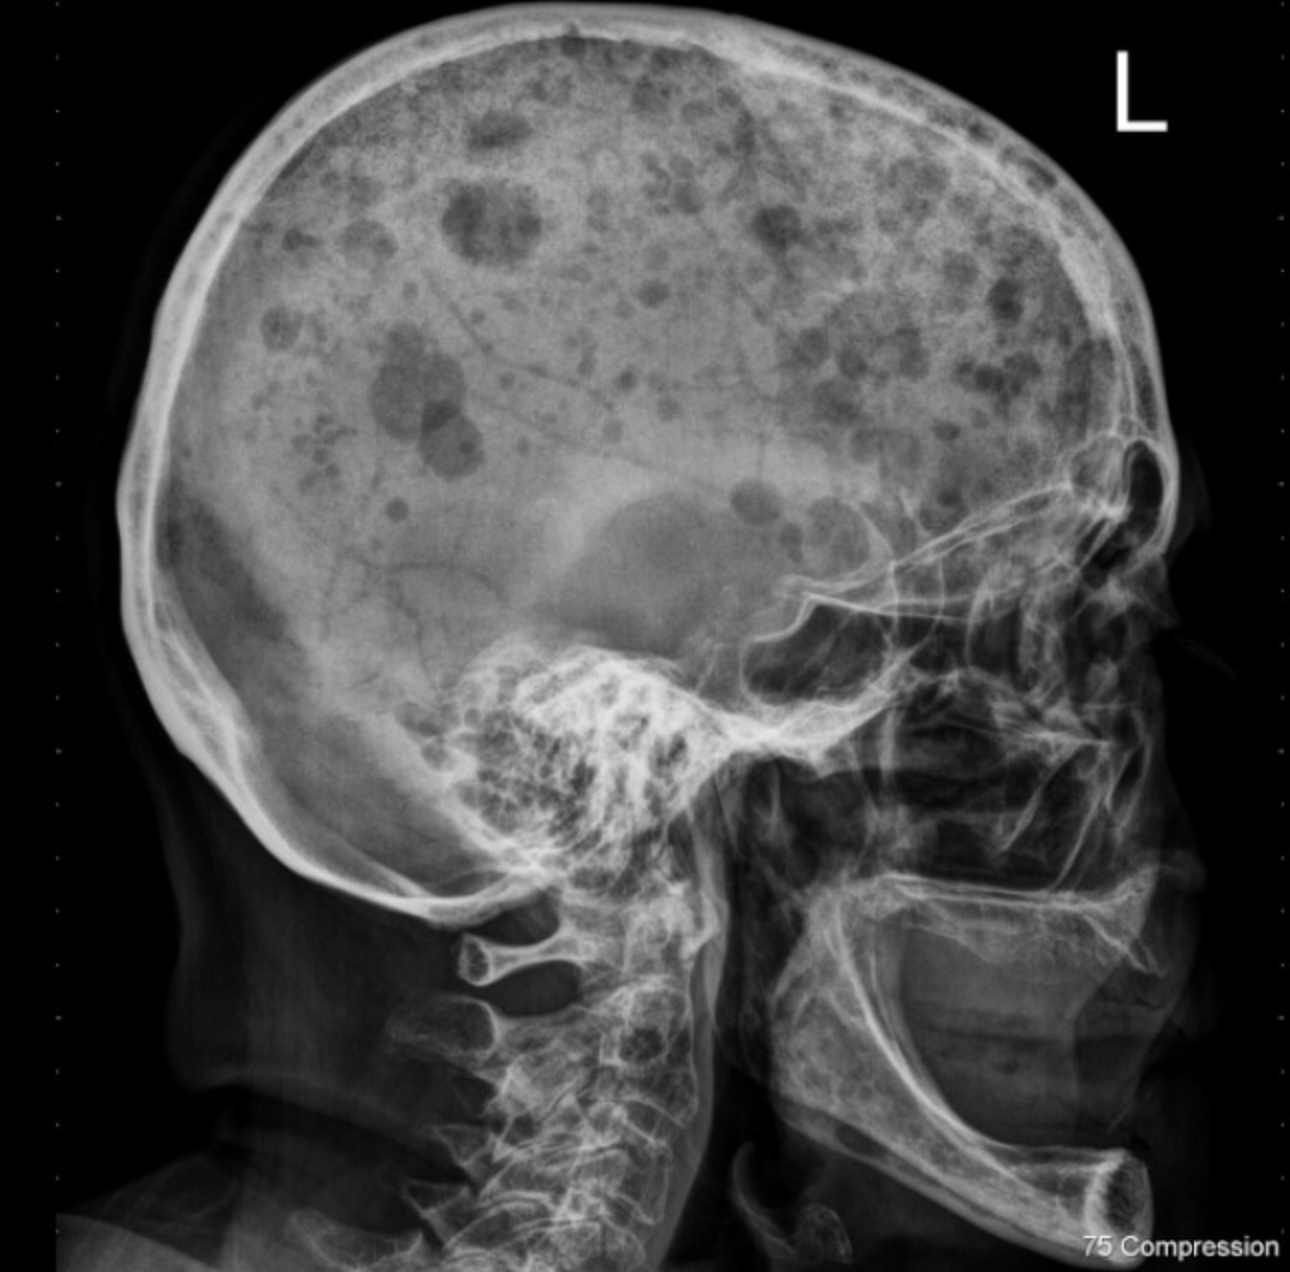

Q

X-ray of the skull shows these “punched out” lesions. The patient is 70 years old, what is a likely diagnosis?

A

Multiple myeloma